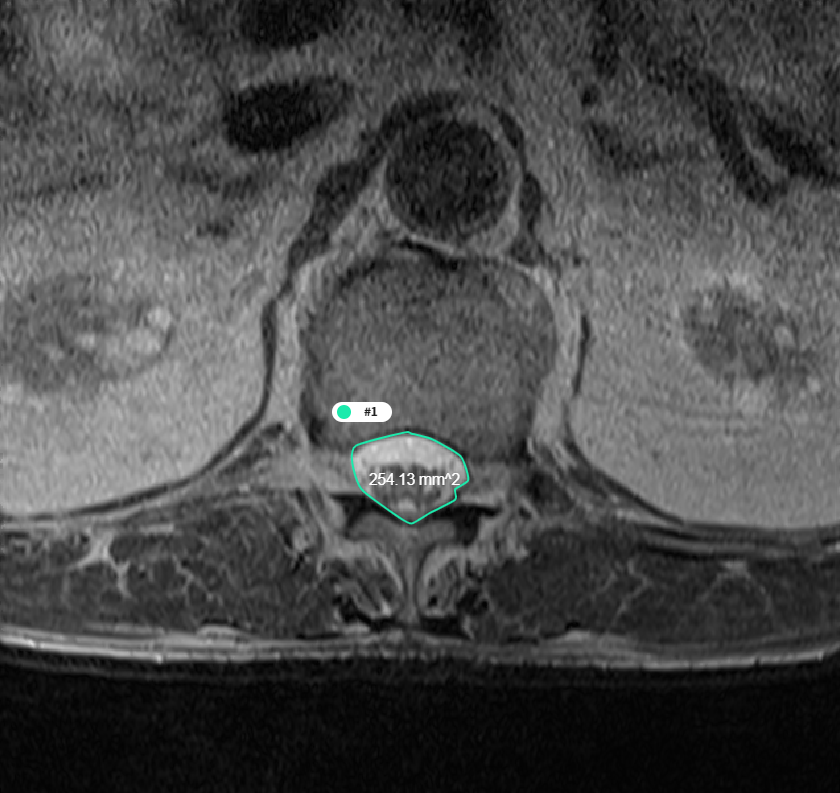

2. 요추 분할 모델 및 디스크 높이 측정 알고리즘

- 모델 학습

- 기존에 널리 이용되는 Segmentation 모델인 U-net architecture를 기반으로 하며, 모델의 Feature 를 찾기 위해 데이터를 다운 샘플링 할때 Crop 및 복사를 해둔 데이터에 Attention Gate 를 적용한 모델.

- 전체 데이터의 20%를 Test에 사용하고, 남은 80%를 10배수 Augmentation 하고, 그 중 60%를 학습에 사용

[사용된 Attention U-Net 아키텍처]

2. 요추 분할 모델 및 디스크 높이 측정 알고리즘 학습(Training) 검증(Validation) 시험(Test) 개요 – Attention U-net 사용 – 학습도중 모델의 성능 평가

– Dice Coefficient Loss 등– 학습 이후 모델의 성능평가

– Dice Coefficient Score 등데이터 비율 23776장 5944장 746장 - Predict 결과물의 각도와 거리 측정

- Predict mask 이미지의 외곽선을 추출하는 contour 기능을 이용하여 4번 5번 요추를 검출하고, 해당 데이터의 각도와 거리 측정

- 측정된 각도와 거리를 실제 측정값과 비교하여 Pearson-Correlation 분석

[요추 4, 5번 간의 디스크 높이 및 각도 측정]

- 척추 면적 측정

- Dicom Header의 Pixel Spacing 정보를 통해 AI 결과에 대한 면적(mm2) 측정

[척추 영역 면적 측정]

데이터 성능 지표 번호 측정항목 AI TASK 학습모델 지표명 기준값 점수 측정값 점수 1 척추 면적 측정(T2 Axial) Object Detection U-Net Correlation 0.75 단위없음 0.83 단위없음 2 디스크 높이 측정 Object Detection U-Net, Attention U-Net Correlation 0.7 단위없음 0.71 단위없음 3 척수 영역 분할(T2 Axial) Image Classification U-Net DSC 0.8 단위없음 0.95 단위없음 4 요추 분할 결과 Image Classification U-Net, Attention U-Net DSC 0.85 단위없음 0.92 단위없음 5 후종인대 골화증 영역 검출 모델 Object Detection YOLO Sensitivity 75 % 81 %